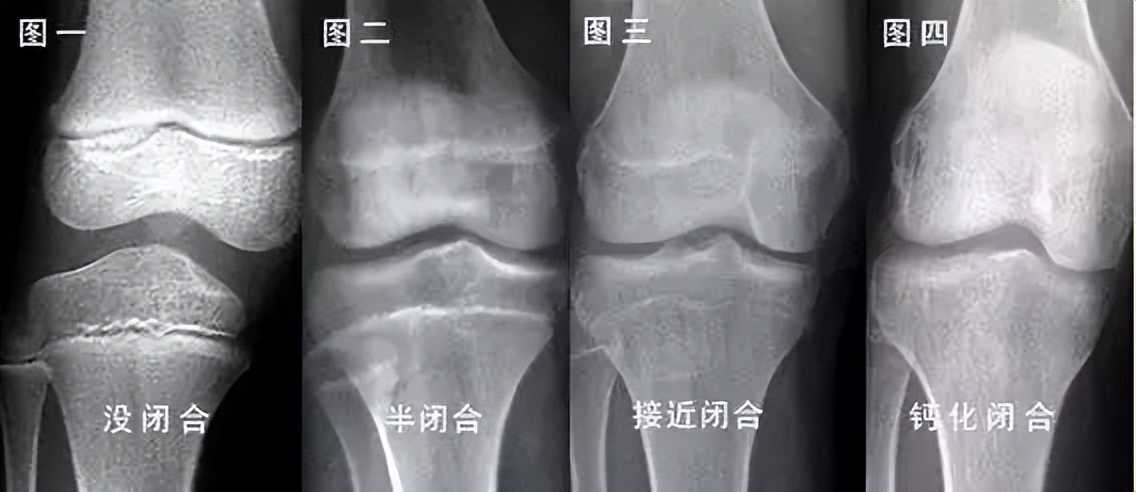

这条线就是 骨骺线 。人的身高,主要是长骨的增长体现的,长骨的最终长度决定了成年后的身高。

多数情况下,只要骨骺线未闭合,就还有长高的机会;反之,当骨骺线闭合时,长骨也就不再生长了,人的身高也就基本定型了。

在骨骺线彻底闭合之前,有 两个长高黄金期 : 3岁以内和青春期 。这两个时期,骨骺线处于开启状态,长骨有足够的生长空间。